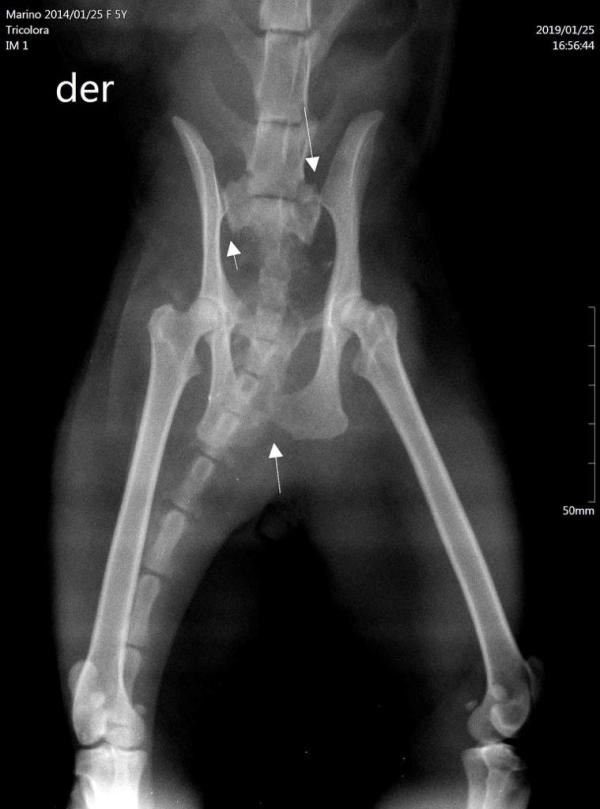

Mi gatita. no sabemos si sufrio un golpe o cayo golpenadose, el informe es que se le corrio la cadra un poco hacia atras, ella no tiene dueño me reconoce porque le doy decomer a horas especificas, no ataca pero se po ne a la defensiva no se deja tocar ha sido casi imposible agarrarla para colocarla en la trasnportadora tapandole la cabeza, ahora esta en mi casa le arme un refugio se esconde debajo de un sofa y hace sus necesidades pero no la veo comer creo toma agua esto sucedio el 22/1 y hoy es 28/1/2019, me han audado pero no tengo experiencia con animales que no son domesticados y que no se dejan tocar, es muy inteligente, se esconde reconoce el lugar y no se si debo dejarla ahi, le pongo las piedras sanitarias y ella va y hace sus necesidades y se retira abajo del sofa la tengo cercada, y por ahora cuando se deja ver la veo bien, no toma la medicacion para dolor y para solidificar sus huesos, pero tampoco se queja se le ve con buen semblante, adjunto foto de placa. mis preguntas son como sigo procediendo, si ladejo que haga su vida se refugie y se alimente, en algun momento si cumple con la sabia naturaleza podra incorporarse, no se cuando pero se que lo hara, gracias por la ayuda